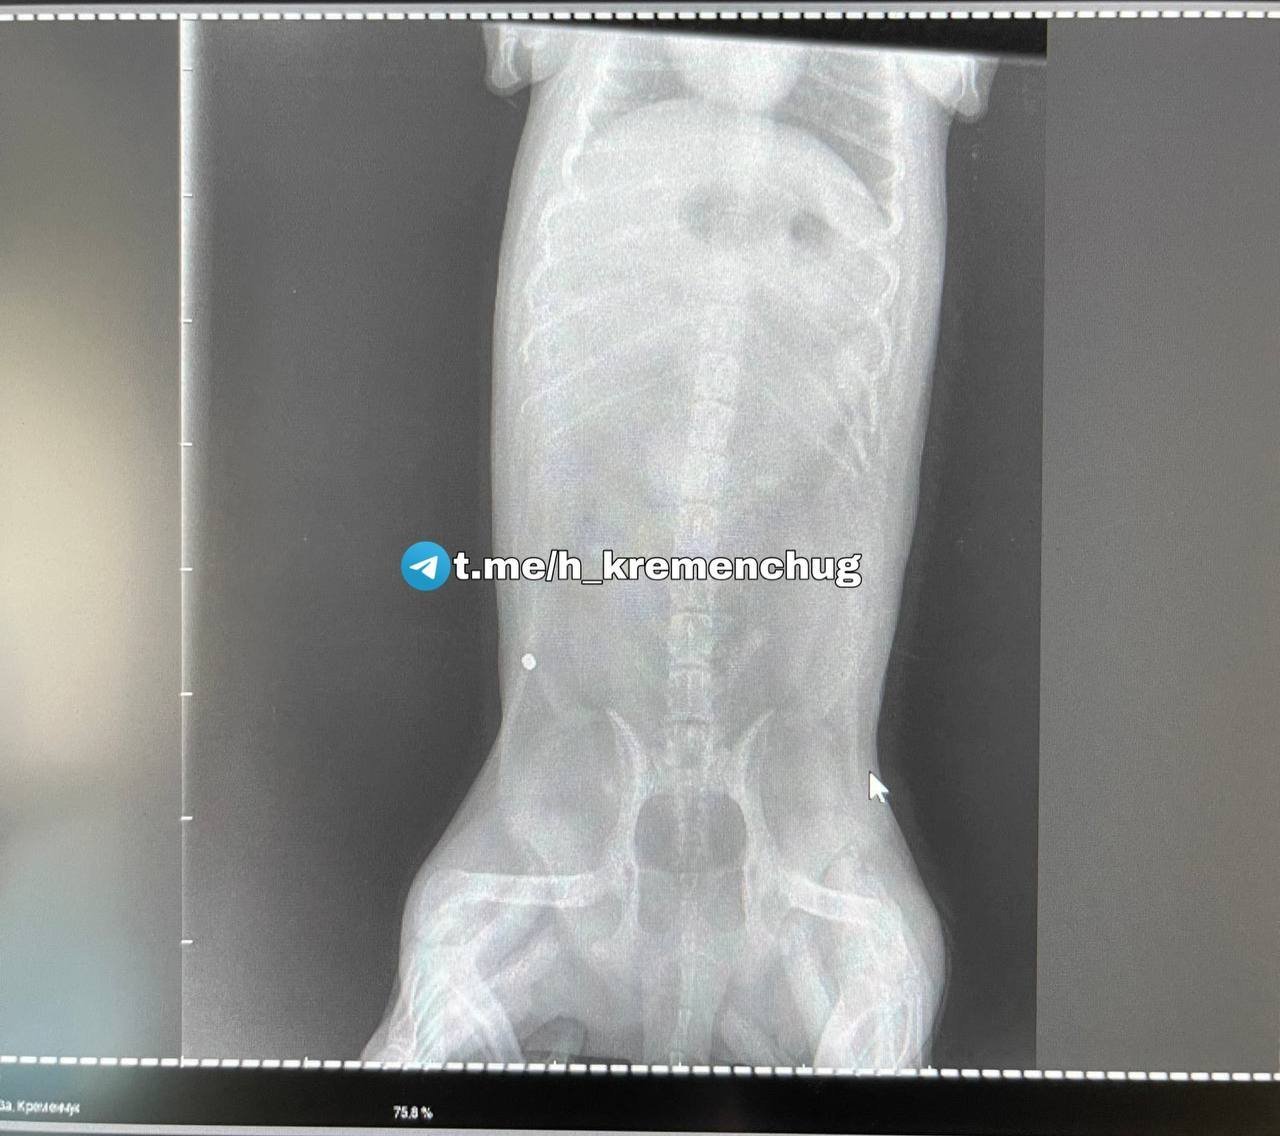

— Ветлікар сказав після операції, що розстріляли з близької відстані. Доказів хто убив, немає, — йдеться у повідомленні.